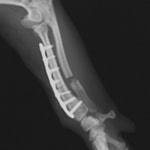

症例:トイプードル 9カ月齢

3ヵ月前より左前肢の跛行が認められるとのことで、来院されました。整形外科学的検査において、患肢の肘関節・肩関節重度の伸展制限が認められました。Xray検査において、左肩関節の内方脱臼、および肩甲骨関節窩の低形成と上腕骨頭の変形が認められました。

数か月に及ぶ慢性脱臼のため、関節面の低形成・摩耗のため整復手術による適切な再建は困難と判断し、切除関節形成術を実施しました。

術後3週間頃より、負重状態、歩行が改善しました。

切除関節形成術は、疼痛を引き起こす関節面を除去し、線維性偽関節の形成により患肢の機能改善を促す救済的手術です。術後のリハビリテーションの実施により、関節の可動域や患肢の筋肉量は改善され、生活の質は向上します。また本症例のように、慢性脱臼だけでなく、重度の骨関節炎症例にも実施することがあります。